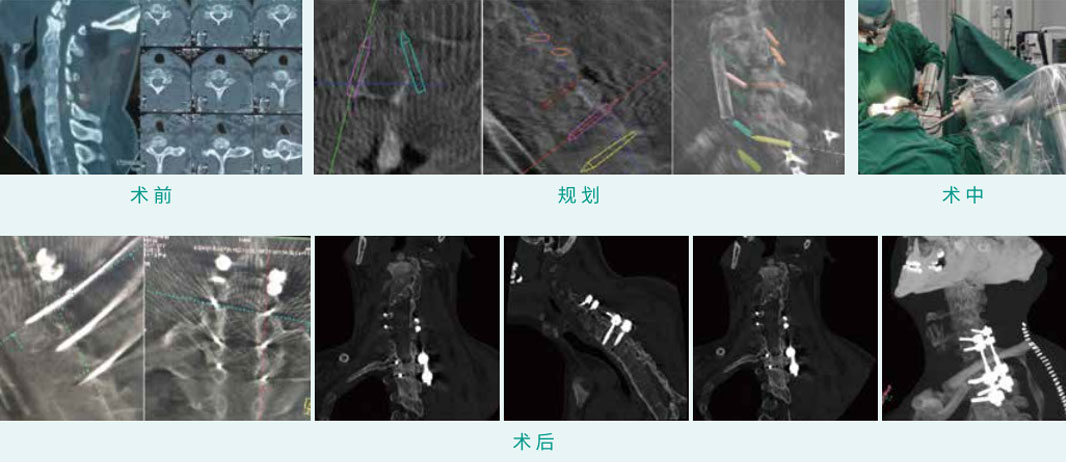

天玑? 辅助C5, C6侧块螺钉内牢靠术合并T1, T2椎弓根螺钉内牢靠术

基本情形:患者男,39岁,颈椎骨折(C2, C7),强直性脊柱炎

机械人累积用时:30分钟

植入物:4枚侧块螺钉,4枚椎弓根螺钉

病例泉源:北京积水潭医院 刘亚军